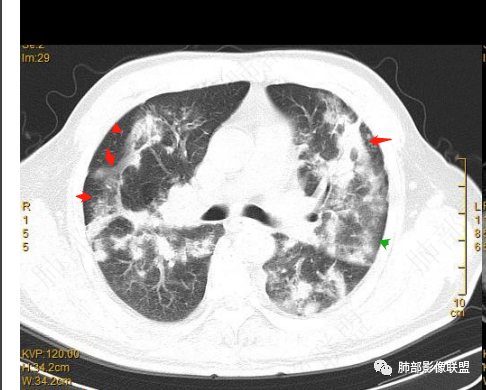

2022.2.17CT显示两肺中内带多发结节影、斑片影、条索影,部分病灶侧向融合与胸膜平行。部分病灶沿着支气管血管束分布、其内支气管稍扩张。部分病灶呈反晕征。大部分病灶边界显示清晰,部分病灶周围可见边界不清的GGO。2022.4.12CT显示两肺中内带多发结节影、条索状、条带状高密度影,边界收缩平直凹陷,大部分病灶沿着支气管血管束分布,亦有位于胸膜下侧向融合与胸膜平行的病灶。总体与第一次CT对比两肺病灶明显吸收。